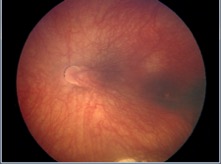

Macular Drag

Because the fovea is one of the terminal points of the visual axis, any pathology that disrupts the foveal anatomic location can lead to alterations to this axis. In entities such as choroidal neovascularization from age-related macular degeneration (AMD), the contour and location of the fovea is altered.[27] Macular translocation was a historical intentional surgical technique in patients with AMD not commonly performed today.[28] [29] Altered optical axes are more commonly seen in pathologies causing drag of the fovea such as in retinopathy of prematurity or familial exudative vitreoretinopathy.

FIGURE 8 -Photo of dragged macula from retinopathy of prematurity causing a shift in angle kappa (Courtesy of Francine Baran, MD)